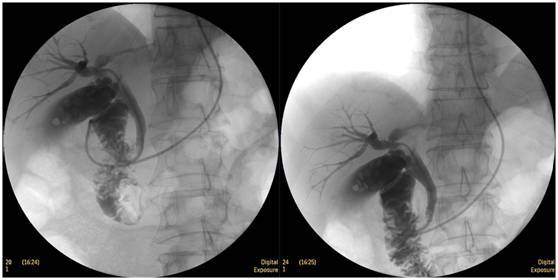

膽總管結(jié)石

柱狀球囊擴張完全,膽總管擴張,下段見充盈缺損影。

膽總管擴張,下段見明顯充盈缺損(上圖為反片且局部放大后效果)

柱狀球囊擴張膽總管下段及乳頭(上圖為使用取石網(wǎng)籃取石)。